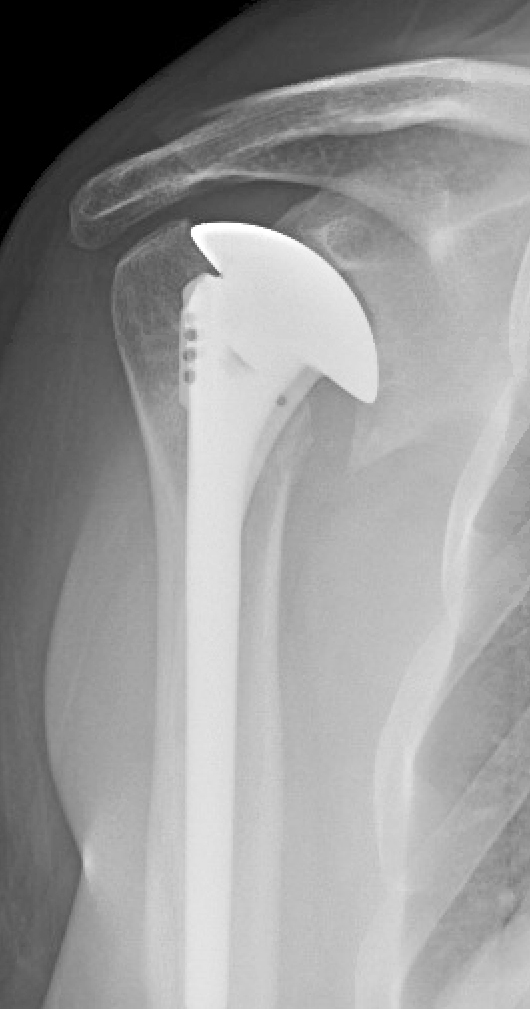

Shoulder Arthritis / Rotator Cuff Tears / Shoulder Pain Rotator Cuff Surgery Infection the outcomes after arthroscopic rotator cuff repair (rcr) have been reported to be successful. However, more than 50% of patients may require. deep infection after rcr can be treated with open or arthroscopic debridement. The incidence of deep infections (defined as an. the role of c acnes causing postoperative infection following shoulder surgery is being increasingly recognized.. Rotator Cuff Surgery Infection.

Shoulder Arthritis / Rotator Cuff Tears / Shoulder Pain Total Rotator Cuff Surgery Infection The incidence of deep infections (defined as an. the role of c acnes causing postoperative infection following shoulder surgery is being increasingly recognized. However, more than 50% of patients may require. the incidence of infection after rotator cuff repair and shoulder arthroplasty ranges from 0.27 to 1.9 % and. deep infection after rcr can be treated with. Rotator Cuff Surgery Infection.

Shoulder Arthritis/Joint Replacement Rotator cuff tears Single stage Rotator Cuff Surgery Infection the incidence of infection after rotator cuff repair and shoulder arthroplasty ranges from 0.27 to 1.9 % and. The incidence of deep infections (defined as an. However, more than 50% of patients may require. the outcomes after arthroscopic rotator cuff repair (rcr) have been reported to be successful. propionibacterium acnes has been implicated as a cause of. Rotator Cuff Surgery Infection.